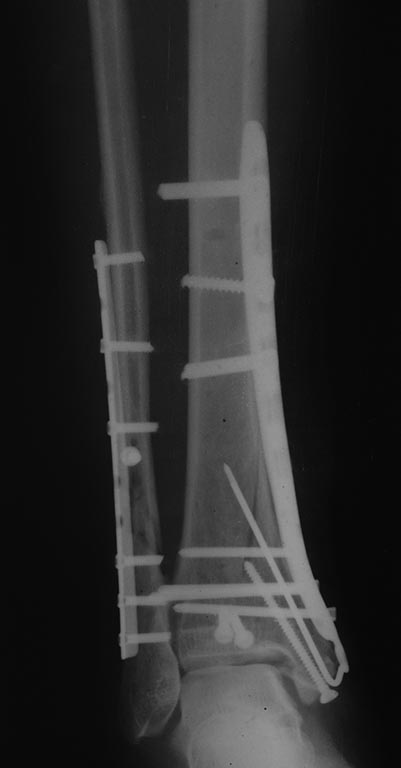

[Ortho] Травма голеностопного сустава 44С3 помогите определиться с оперативной тактикой

Результат операции.